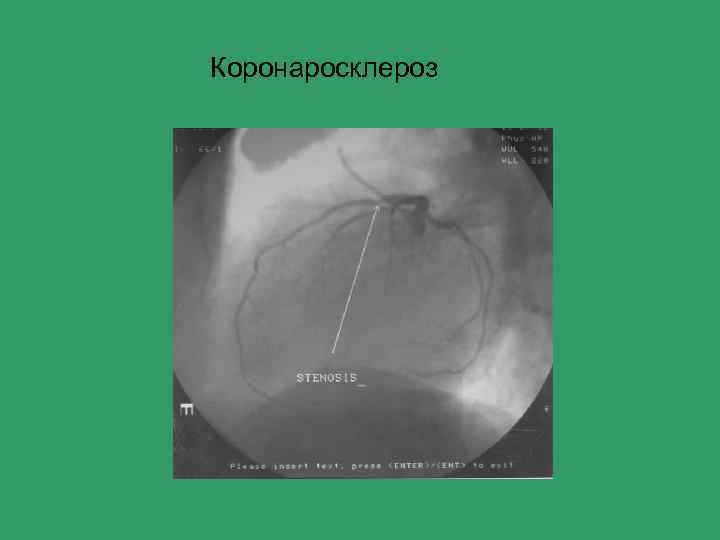

Коронаросклероз